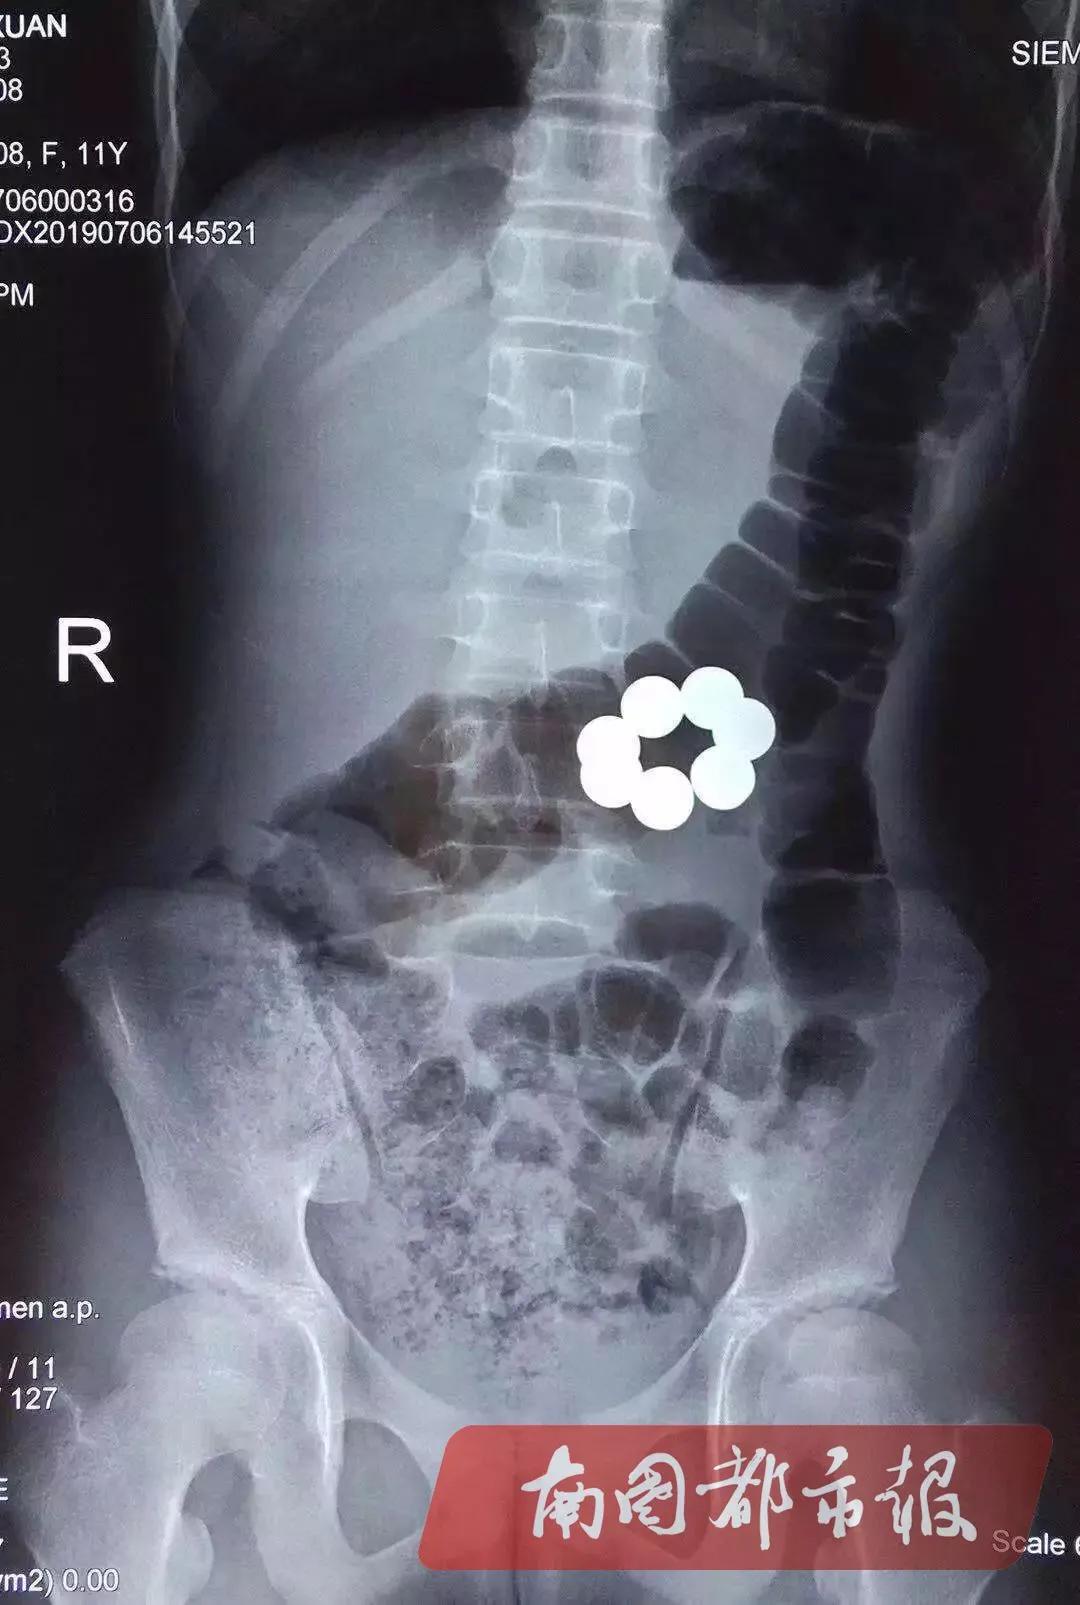

随后,符医生让小芳做X光检查,检查结果显示,由于磁力珠有磁性,肚子里7颗珠子已首尾相接,呈串珠样,所以无法排出。为了弄清7颗珠子的具体位置,又建议小芳做超声检查。超声科医生覃伶伶表示,经过超声精准定位,7颗珠子在十二指肠远端和空肠近端,形成了不完全肠梗阻。